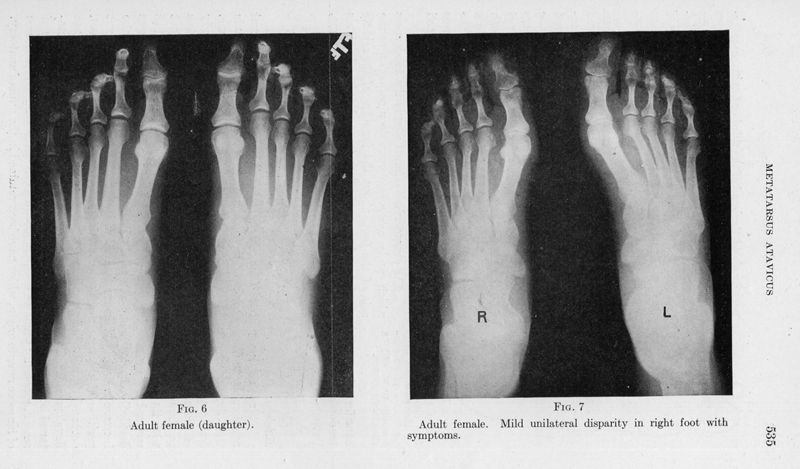

Metatarsus atavicus. The identification of a distinctive type of foot disorder

In : [The] Journal of bone and joint surgery, 1927, Vol. 9, pp. 531-44